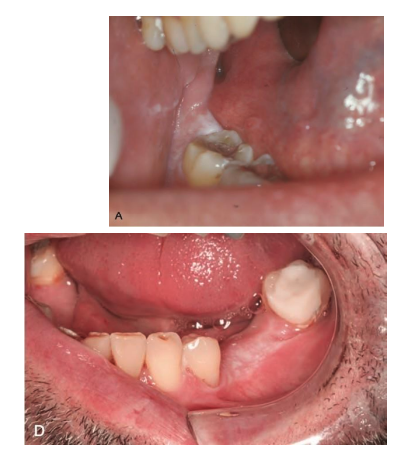

How many of these leukoplakias become/are dysplasia/SCC?

25-47%

Variable malignant transformation

Homogenous: 16%

Proliferative leukoplakia: 70-100%